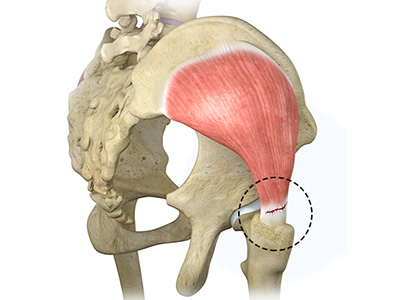

- Gluteals: These are the muscles that form the buttocks. There are three muscles (gluteus minimus, gluteus maximus, and gluteus medius) that attach to the back of the pelvis and insert into the greater trochanter of the femur.

Hip Dislocation Gluteus Tendon Tear

Gluteus Tendon Tear Hip Abductor Tears

Hip Abductor Tears Hamstring Injuries

Hamstring Injuries Gluteus Medius Tear

Gluteus Medius Tear Hip Pain